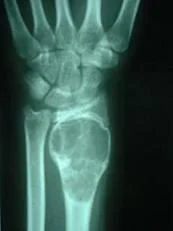

La Displasia del Desarrollo de la Cadera ó Displasia Evolutiva de la Cadera, es un problema dinámico que abarca un amplio espectro de condiciones patológicas, clínicas y radiológicas, que incluyen desde  la cadera luxada, subluxa y la inestable, pasando por la displasia o alteración del desarrollo acetabular o de la cabeza del fémur. Ver más.